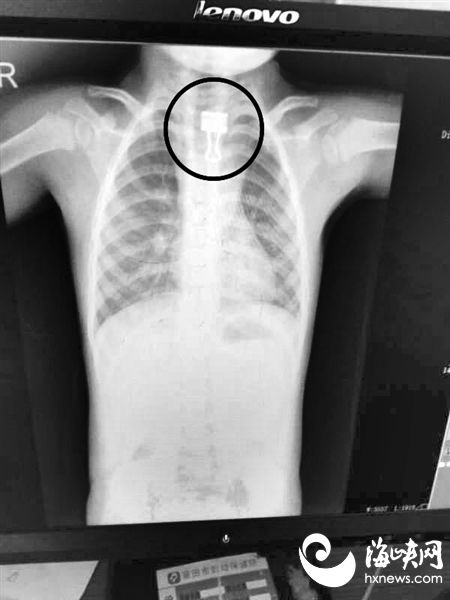

12日凌晨0时许,文文被送到莆田市第一医院的时候已是深夜,接诊文文的是消化内科副主任医师魏建雄。经检查,医生发现文文吞下的燕尾夹长约4厘米,燕尾夹卡在咽喉和食管交界处。魏建雄医生告诉海都记者,考虑到文文年龄较小,食管腔较为脆弱狭小,而吞下的燕尾夹又不规则,稍微不慎就可能导致气管破裂,进而危及生命,所以需要及时取出。